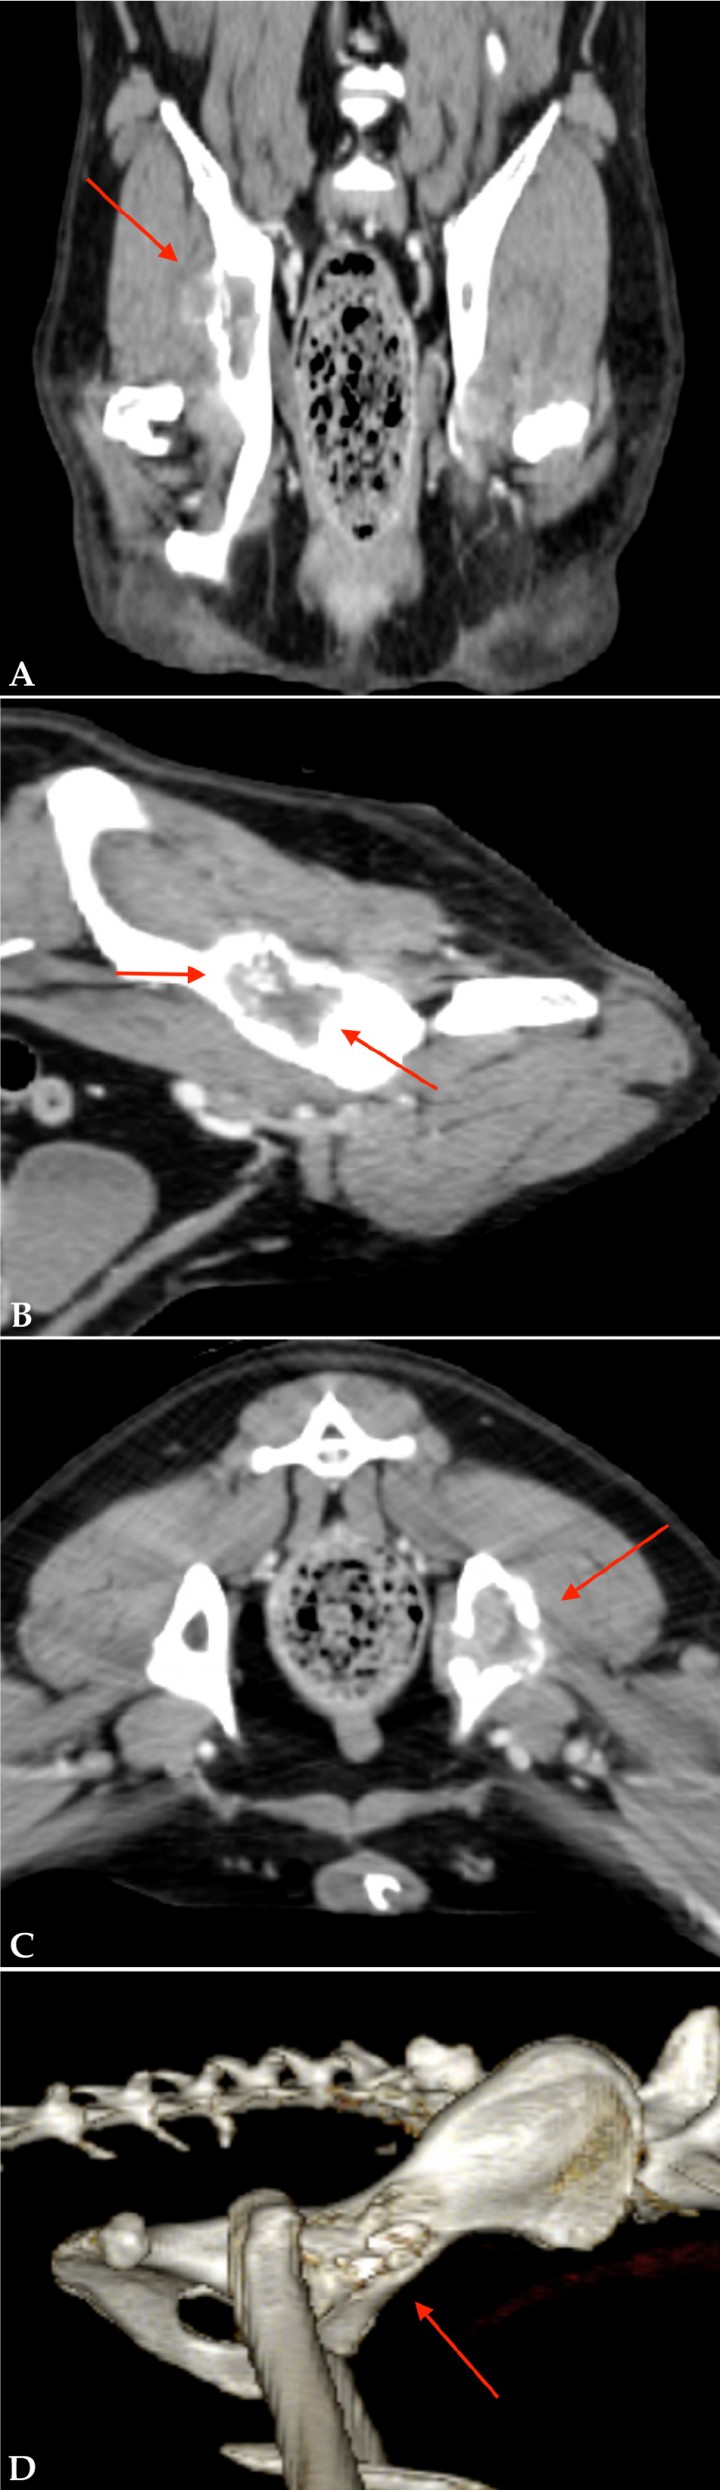

Se observó una lesión monostótica en el ilion, con afectación del acetábulo, compatible con neoplasia ósea primaria. Se visualizó también una lesión glútea profunda derecha compatible con invasión neoplásica, aunque no se podría excluir inflamación y/o edema (Fig. 2).

(A) Imagen coronal del TC. (B) Imagen sagital del TC. (C) Imagen axial del TC. Se observa una lesión monostótica osteolítica y osteoproliferativa en el ilion, con afectación del acetábulo, compatible con neoplasia ósea primaria (flechas rojas). (D) Reconstrucción 3D de la lesión iliaca con afectación del acetábulo compatible con neoplasia ósea primaria.